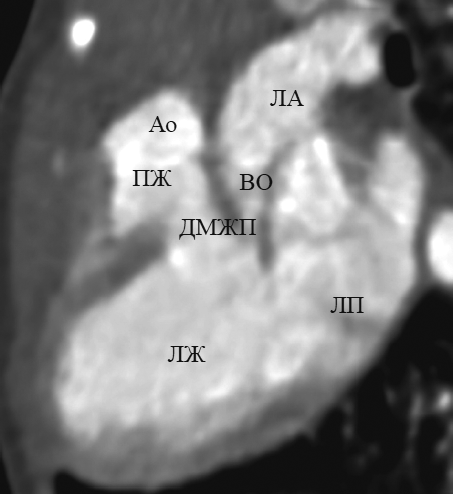

This article contents the results of computed tomography with intravenous bolus contrast media administration data analysis in children with transposition and congenitally corrected transposition of the great arteries with the consequental performing of the multiplanar heart-axis-oriented reformations. Among 148 examined children transposition of great arteries was detected in 13 patients (9 boys and 4 girls aged 1-144 day of life); congenitally corrected transposition was found in 4 cases of children aged from 6 months to 15 years and 6 months (2 boys and 2 girls). In this article comprehensive anatomical criteria of each heart chamber morphology are presented and reformations where these criteria can be seen are shown. Also in the article is given comparative characterization of heart and great arteries structures in transposition and congenitally corrected transposition in every certain heart-axis-oriented reformation. By the results of consequently performed heart-axis-oriented reformations data analysis the peculiar anatomical signs of transposition and congenitally corrected transposition are determined. The results of data analysis show that from the list of offered reformations the peculiar anatomical signs of both kinds of transposition are significantly determined in long-axis of right ventricle inflow tract reformation, left heart chambers reformation, supply ventricle division reformation, short-axis reformation at the level of great arteries. Computed tomographic angiocardiography heart-axis-oriented multiplanar reformations permit full and correct assessment of heart and main vessels, which is important for planning of surgical treatment in congenital heart diseases.